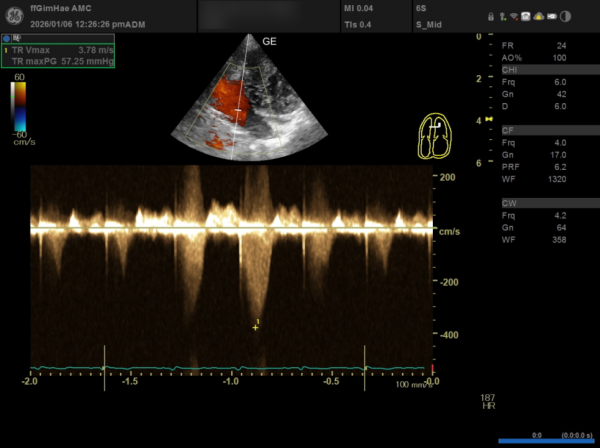

① TR(삼첨판 역류) 수치

TR Vmax: 3.78m/s (기준치인 3.4m/s를 훨씬 초과)

TR maxPG: 57.25mmHg